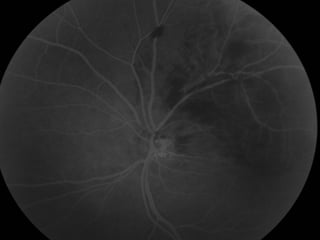

Retinografia 10/02/2009

Caso Clínico

Angiografia 10/02/2009

Caso Clínico Exame Oftalmológico: AcuidadeVisual c/c: • OD = 20/20 • OE = 20/100 (metamorfopsias) • Add: +3,00 Biomicroscopia: Normal FO: OD: Normal. OE: Hemorragias retinianas temporal superior. Edema Macular Solicitado: Angiografia e OCT